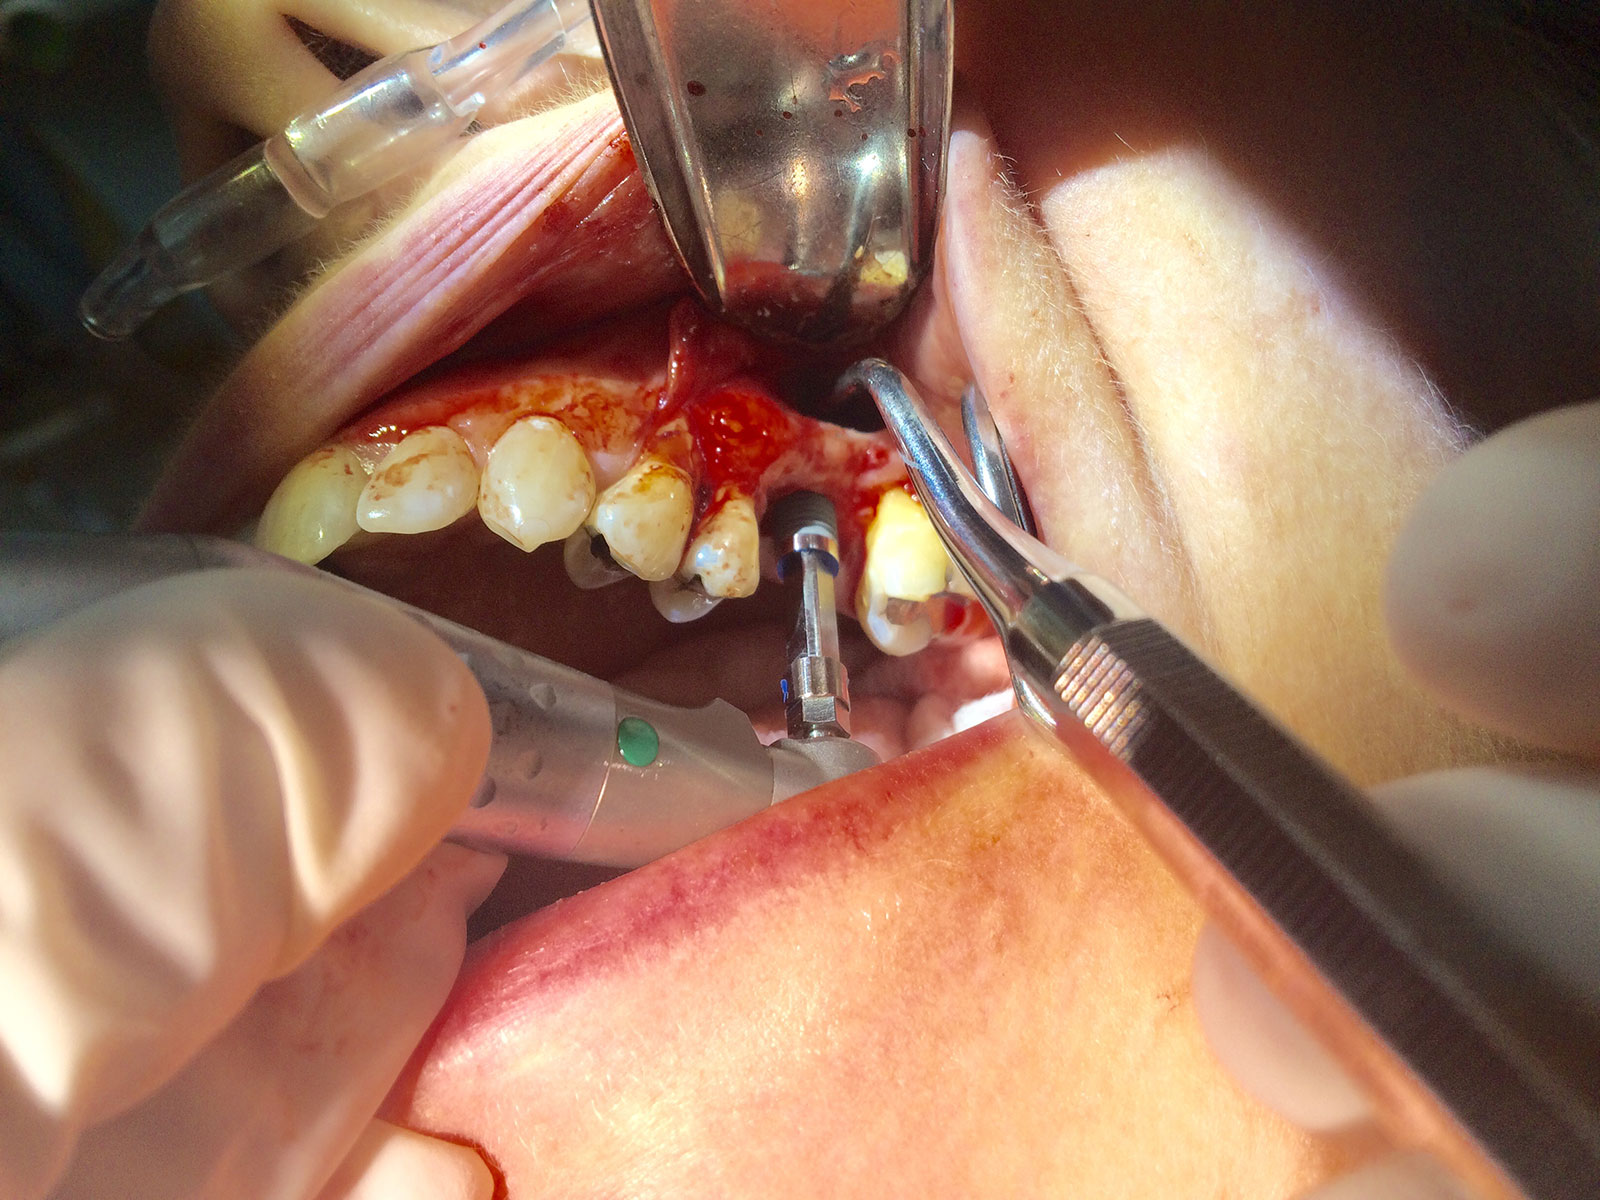

Sinus Grafting Procedures

A sinus grafting procedure, also known as a sinus augmentation, is for patients who have insufficient natural bone in the areas where dental implants are needed. They are long lasting, strong and sturdy, and fit and function like natural teeth. The procedure involves adding bone, either your own natural bone from another part of the body, from a donor or made of processed or synthetic bone material, and placing it below the sinus so that the implants can be placed. After the bone has healed and developed, usually around four to 12 months, the dental implants can be placed.

The photos on this website are from real surgeries performed by Dr. Ulloa. Due to the

graphic nature of the images and content, viewer discretion is advised.